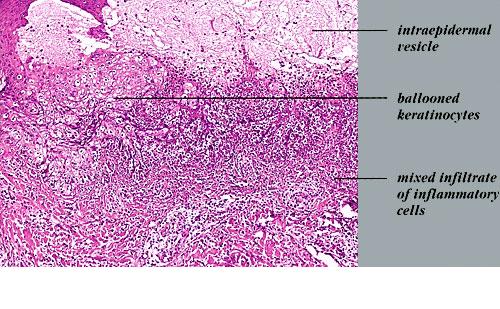

Vaccinia =الوقس =جدري البقر